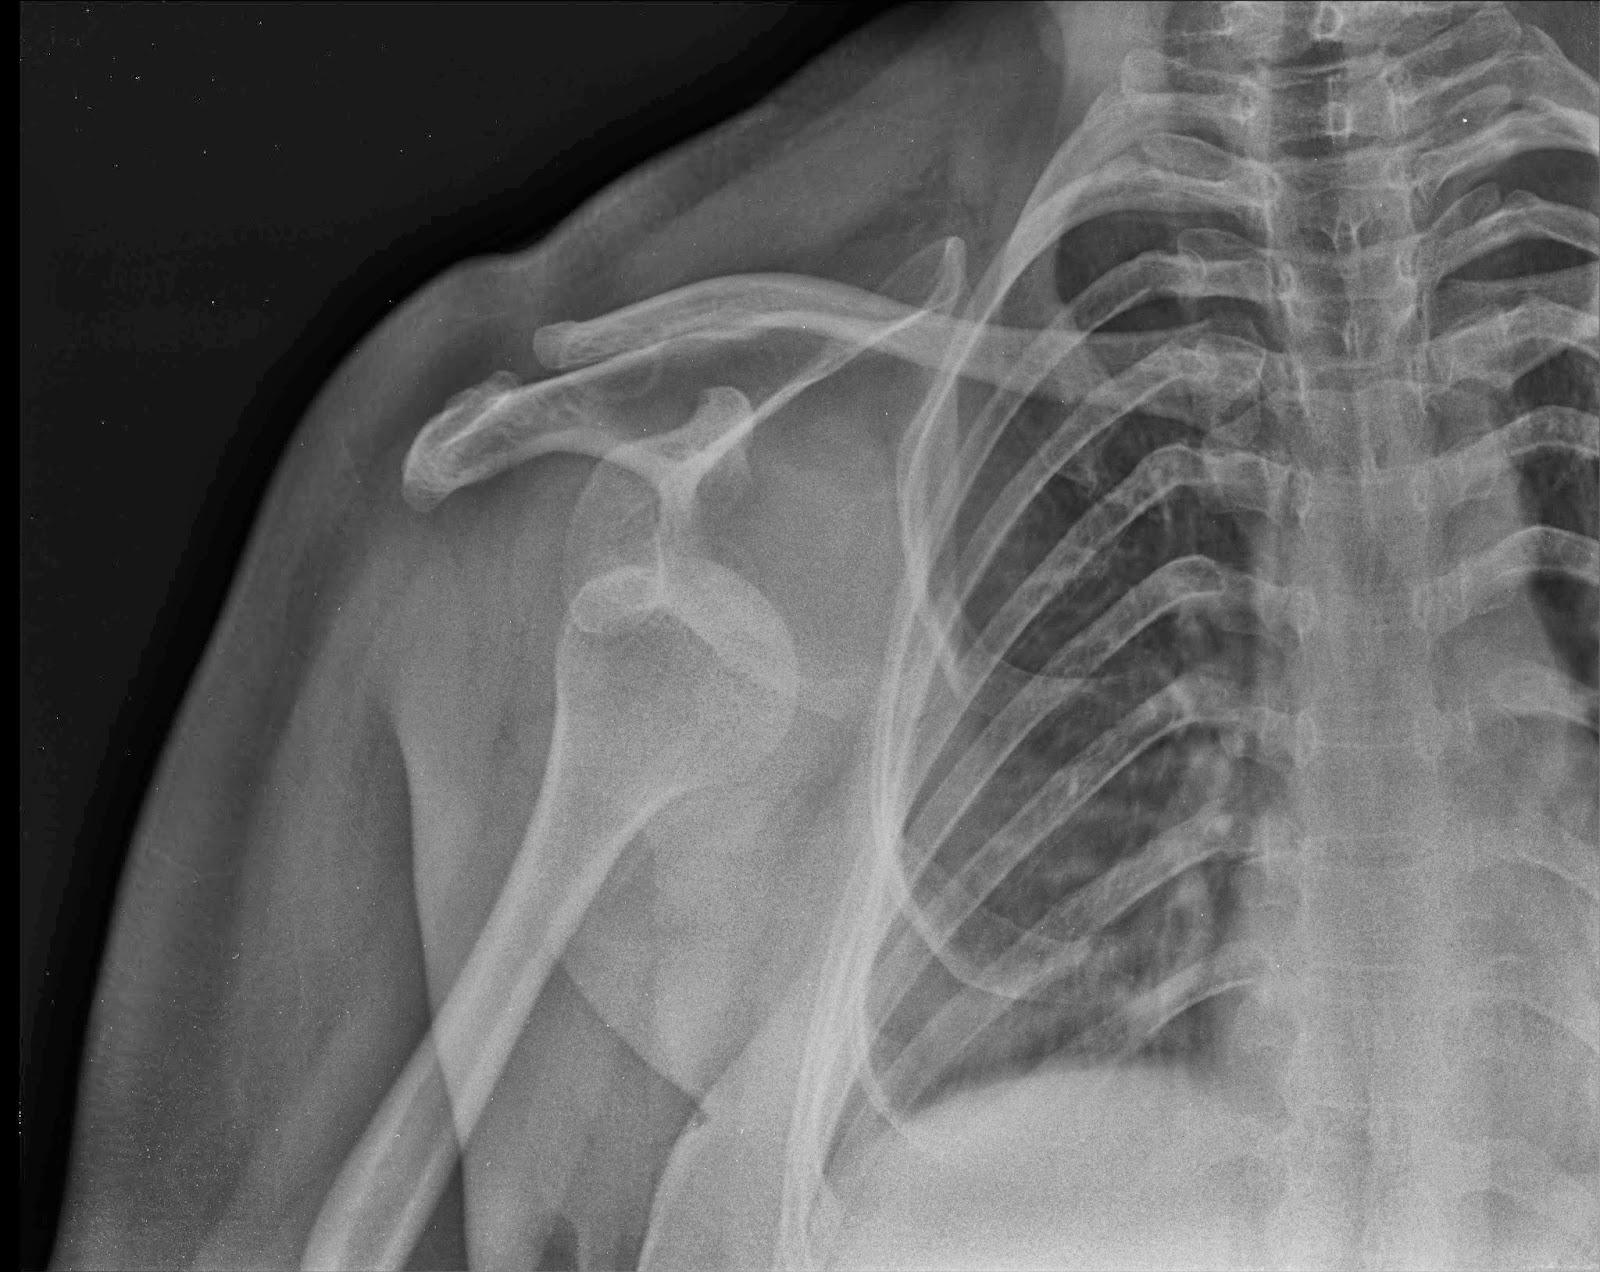

X Ray Axillary Shoulder View . This view provides excellent visualization of the humeral head and neck, though it is typically painful for the patient since it requires shoulder abduction. C, the grashey or posterior oblique view is a tangential view of the glenohumeral joint obtained with 35° posterior rotation of the shoulder. Clinicians typically use the axillary view in evaluating subluxations and dislocations of the humeral head, generally centered on the glenoid and. The shoulder series is fundamentally composed of two orthogonal views of the glenohumeral joint including the entire. 5 playlists include this case public playlists In most clinical scenarios this refers to a radiograph of the glenohumeral joint. The axillary and y views are second views that are used in the assessment of shoulder/ glenohumeral dislocation. Hooked acromion is associated with impingement and rotator cuff pathology.